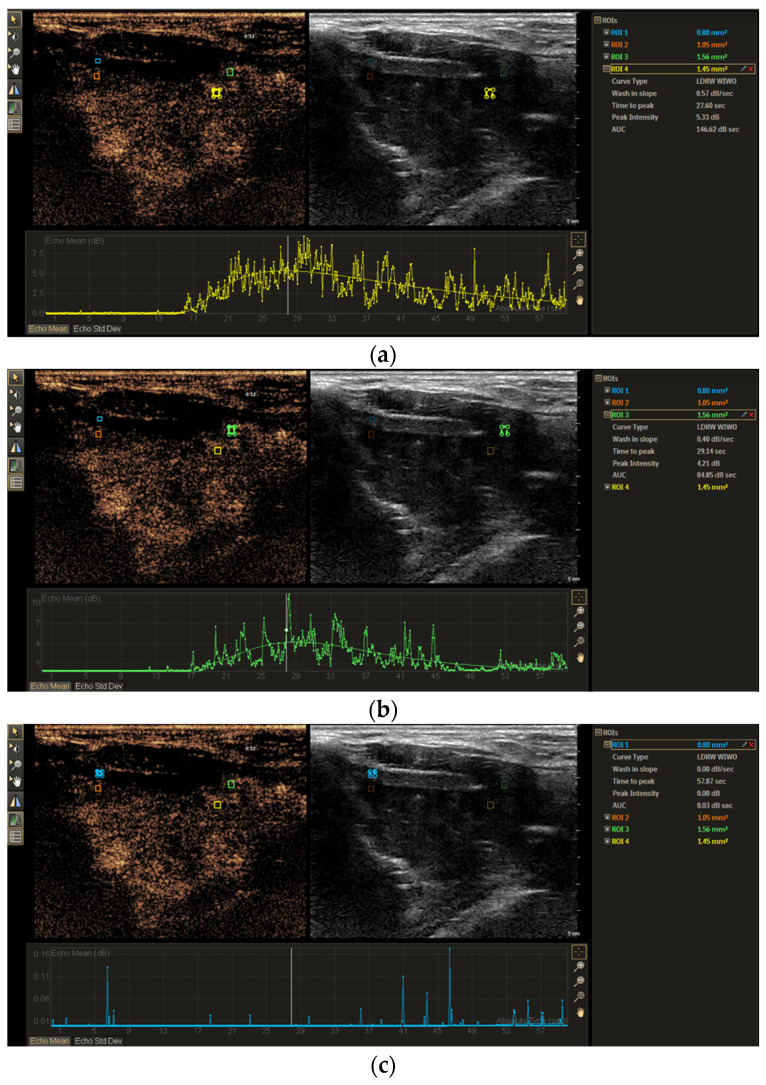

Objective: This study aimed to assess the diagnostic value of contrast-enhanced ultrasound (CEUS) time-intensity curve (TIC) parameters in detecting non-ossified thyroid cartilage invasion in patients with laryngeal squamous cell carcinoma (SCC). Methods: A CEUS TIC analysis was performed on 32 cases from 27 patients with histologically confirmed laryngeal SCC. The diagnostic performance of time to peak (TTP), peak intensity (PI), wash-in slope (WIS), area under the curve (AUC), and their quantitative differences (∆TTP, ∆PI, ∆WIS, and ∆AUC) to discriminate between the invaded and the non-invaded non-ossified thyroid cartilage was determined using ROC analysis. A logistic regression analysis was employed to identify significant predictors. Results: In an ROC analysis, of all TIC parameters analyzed separately, ∆TTP showed the greatest diagnostic performance (AUC: 0.85). A ∆TTP cut-off of ≤ 8.9 s differentiated between the invaded and the non-invaded non-ossified thyroid cartilage with a sensitivity of 100%, specificity of 76.9%, and accuracy of 81.3%. A combination of ∆TTP and PI increased the AUC to 0.93, specificity to 100%, and accuracy to 96.8%, but reduced the sensitivity to 83.3%. Meanwhile, the visual assessment of enhancement on CEUS to detect cartilage invasion had 83.3% sensitivity and 84.6% specificity. In a univariate logistic regression, only ∆TTP was a significant predictor of non-ossified thyroid cartilage invasion (OR: 0.80; 95% CI: 0.64-1.00). For every second increase in ∆TTP, the probability of thyroid cartilage invasion decreased by 20%. Conclusions: CEUS TIC parameters, particularly a combination of ∆TTP and PI, showed high diagnostic performance in the detection of non-ossified thyroid cartilage invasion in laryngeal SCC.

Abstract Image